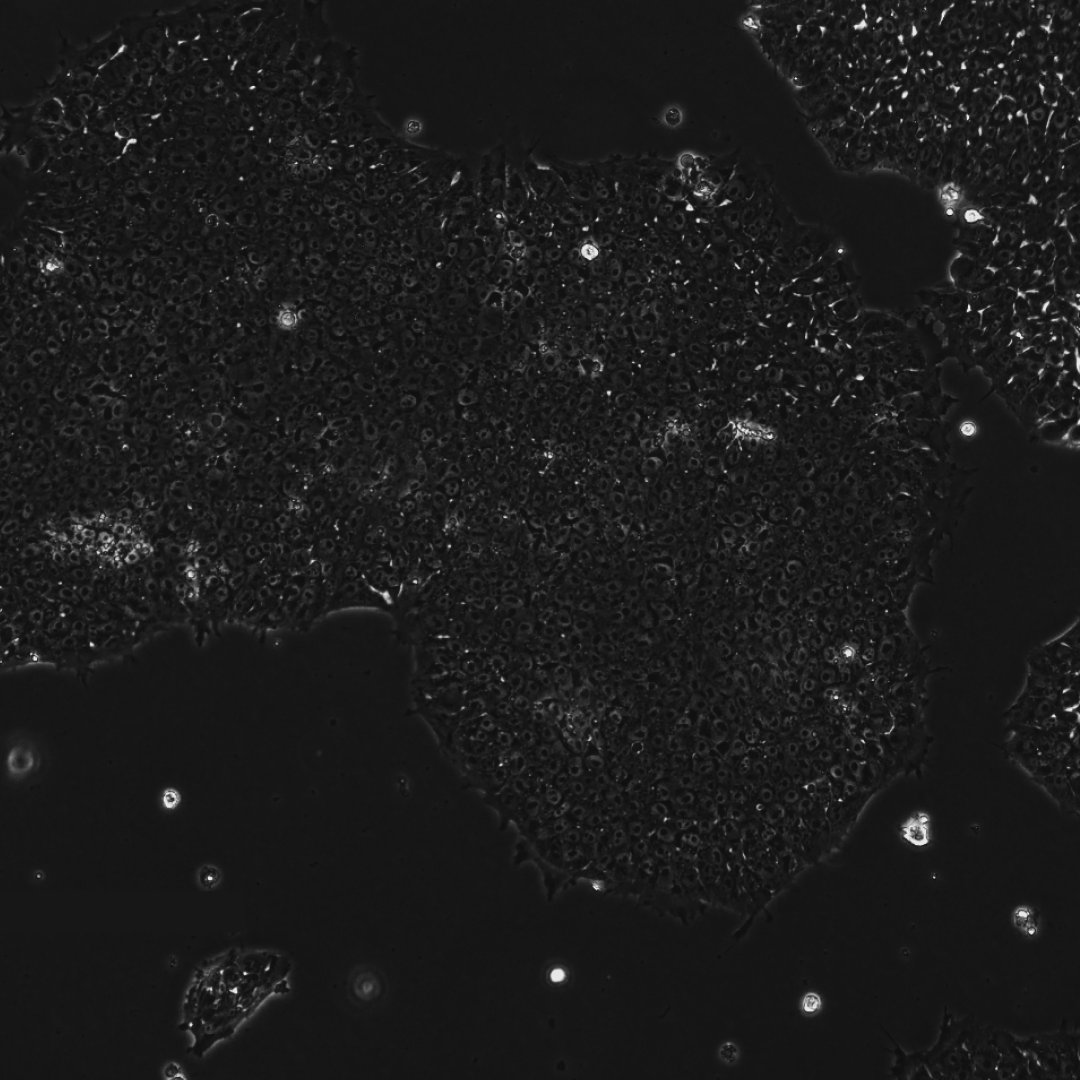

下面这三张图展示的是,OpenAI 设计的蛋白质能更高效地诱导干细胞重编程:

为了进一步确认重编程效率的提升并探索其临床应用潜力,研究团队测试了一种新的递送方式(使用 mRNA 替代病毒载体)和另一种细胞类型 —— 源自三位中年(50 岁以上)捐赠者的人类间充质基质细胞(MSCs)。

仅 7 天内,便有超过 30% 的细胞开始表达关键的多能性标记物(SSEA4 和 TRA-1-60)。

到第 12 天,已出现大量形态与典型 iPSC 相似的集落。这些细胞中超过 85% 激活了包括 OCT4、NANOG、SOX2 和 TRA-1-60 在内的关键干细胞标记物的内源性表达。

接着,研究团队验证了这些由 RetroFactor 衍生的 iPSC 能够成功分化为全部三个主要胚层(内胚层、外胚层和中胚层)。

此外,研究团队将多个单克隆 iPSC 细胞系传代培养,证实了其具有健康的核型和适用于细胞疗法的基因组稳定性。

这些结果全面超越了由合同研究组织(CRO)使用标准因子生成的常规 iPSC 细胞系的基准数据,进一步证明了研究团队工程化变体的稳健性,也为其在不同递送方式和细胞类型中的应用提供了有力证据。

下面三张图中所有的结果共同证实了,研究团队已成功获得健康、且完全重编程的干细胞,从而也全面验证了重编程干细胞的健康与功能。